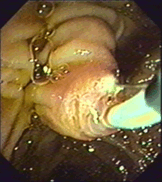

Рисунок 14 – А –папиллотомная петля; Б – ЭПСТ

Суть операции: чтобы нормализовать отток желчи или извлечь конкремент из желчных путей, необходимо расширить выходной отдел общего желчного протока, который представлен большим дуоденальным сосочком. Это достигается путем рассечения его вверх по продольной складке (интрамуральная часть холедоха, до 1,5 см) специальной струной или иглой папиллотома под действием электротока (вводится через инструментальный канал эндосокопа). Если камень небольшого диаметра, то после ЭПСТ он выходит самостоятельно. В случаях, когда размеры конкрементов превышают диаметр просвета нижележащих отделов желчных путей, то не происходит спонтанного отхождения конкрементов после ЭПСТ. Тогда необходимо насильственное их извлечение при помощи специальной корзинки Дормиа (литоэкстракция).